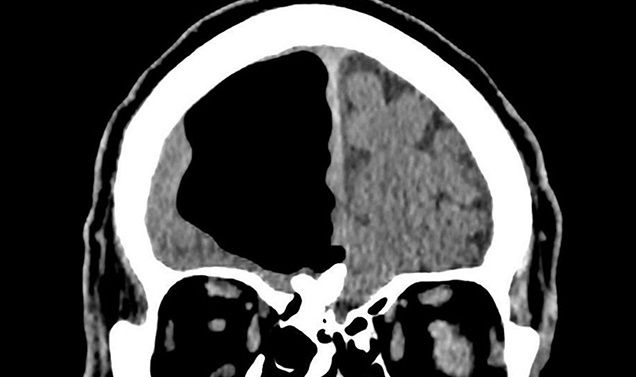

Un hombre de 84 años sorprendió a un grupo de médicos que hallaron un gran hueco de aire en el lugar donde debería ir su cerebro.

Según informó Washington Post, el espacio anormal medía cerca de nueve centímetros y es algo común en pacientes que han tenido cirugía cerebral, aunque en tamaños mucho menores. El fenómeno también podría producirse por infecciones nasales o por golpes faciales.

No fue hasta que le realizaron tomografías cuando notaron el hueco de aire en el lóbulo frontal derecho de su cabeza: una parte de su cerebro estaba desaparecida.